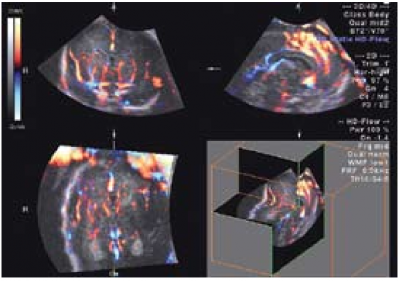

העל-שמע התלת ממדי הוא שיטת הדמיה יעילה להערכת המוח: מתמרים בטניים ונרתיקיים משמשים לאיסוף חתכים מרובים ויצירת נפח עם דופלר תלת ממדי, המדגים את המבנה המרחבי של כלי הדם התוך גולגולתיים[15].